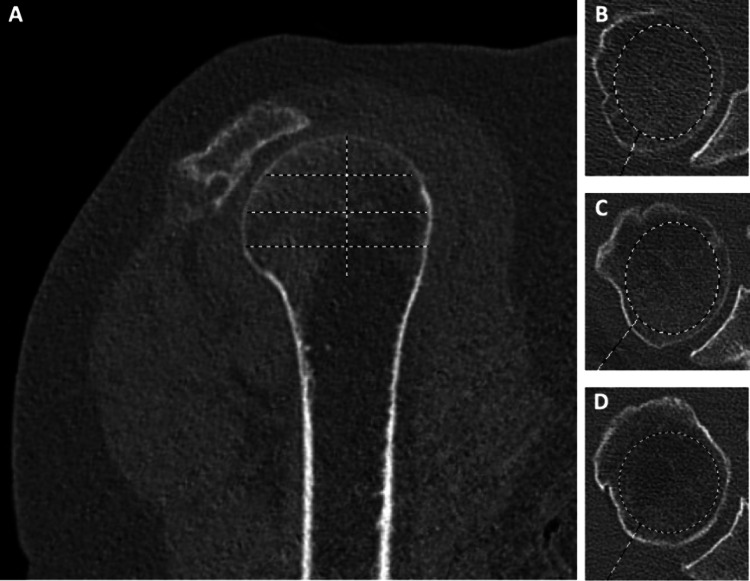

Recent findings: Emerging data surrounding perioperative use of anti-osteoporosis medications for patients undergoing shoulder surgery have not shown definitively favorable or unfavorable outcomes. Similar evaluations in animal studies have shown promising results as a biologic augment to tendon and bone healing, especially with newer, anabolic agents. The mainstay of bone health management remains pre-operative evaluation, using opportunistic radiographic and CT based validated measurements, along with optimization of risk factors. Surgical techniques continue to incorporate implants that perform well in osteopenic bone. Promising pre-clinical studies have identified anabolic anti-osteoporosis medications as viable biologic augments to shoulder surgery, which has not been borne out in any clinical studies at this time.